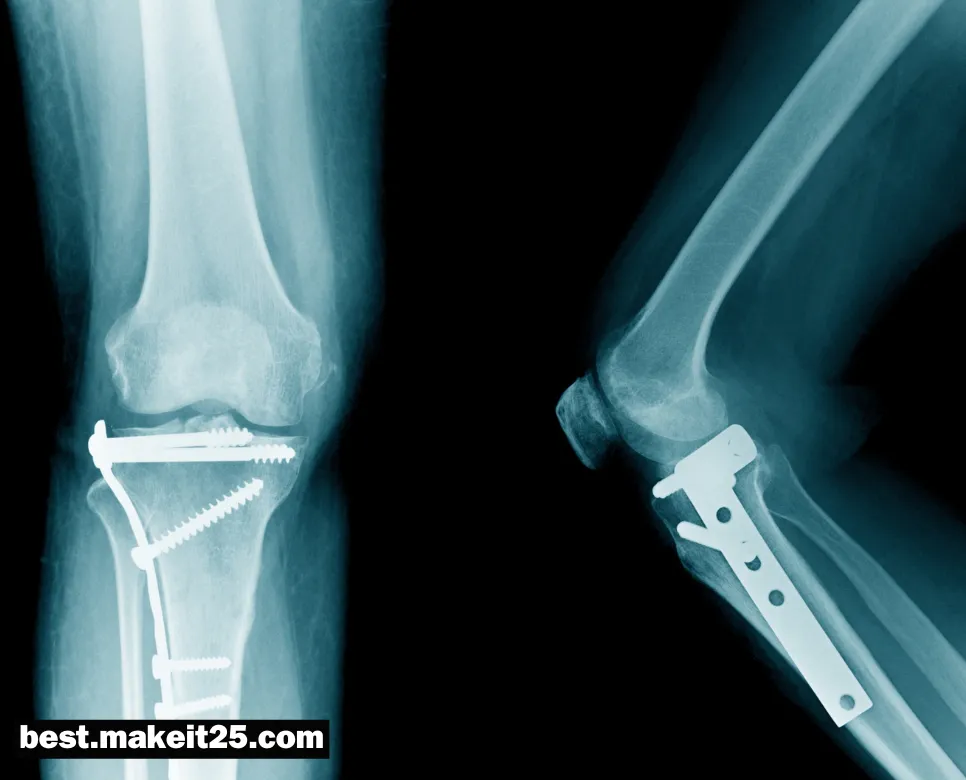

ORIF(관혈적 정복 및 내고정술)

ORIF는 “Open Reduction and Internal Fixation”의 약자로, 골절 치료의 한 방법입니다. 한글로는 “관혈적 정복 및 내고정술”로 번역됩니다. 이 수술 기법은 골절된 뼈를 직접 노출시켜 정렬하고(관혈적 정복), 내부에 금속 임플란트를 삽입하여 고정하는(내고정) 것을 말합니다. ORIF는 복잡한 골절, 전위가 심한 골절, 비관혈적 정복이 어려운 경우 등에 주로 사용됩니다.

- 골절 부위 노출: 골절된 부위를 절개하여 골편을 직접 시야에 노출시킵니다. 이를 통해 정확한 정복과 고정이 가능해집니다.

- 관혈적 정복: 골편을 해부학적 위치로 정렬하고 정복합니다. 이 과정에서 골편 사이에 끼인 연부조직을 제거하고, 필요 시 골이식을 시행할 수 있습니다.

- 내고정: 정복된 골편을 유지하기 위해 내부에 금속 임플란트(금속판, 나사, 핀, 골수정 등)를 삽입하고 고정합니다. 이를 통해 골절 부위의 안정성을 확보하고 조기 관절 운동을 가능하게 합니다.

- 창상 봉합 및 술후 관리: 수술 부위를 봉합하고 적절한 드레싱을 시행합니다. 술후에는 감염 예방, 통증 조절, 기능 회복을 위한 재활 치료 등이 이루어집니다.

ORIF의 장점과 단점

- 장점: ORIF는 해부학적 정복과 안정된 내고정을 통해 빠른 골유합과 기능 회복을 도모할 수 있습니다. 또한, 조기 관절 운동이 가능하여 관절 강직을 예방할 수 있습니다.

- 단점: ORIF는 관혈적 수술로 인한 연부조직 손상, 감염, 출혈 등의 합병증 위험이 있습니다. 또한, 내고정물로 인한 이물감, 통증, 내고정물 실패 등의 문제가 발생할 수 있습니다.

- 사지 골절: 대퇴골, 경골, 상완골, 전완부 골절 등에 ORIF가 널리 사용됩니다.

- 관절 주위 골절: 과간절, 주관절, 족관절 등의 관절 주위 골절에서 ORIF를 통해 관절면을 정확히 정복하고 견고하게 고정할 수 있습니다.

ORIF는 다양한 골절 치료에 활용되는 중요한 수술 기법입니다. ORIF의 성공을 위해서는 숙련된 술기, 적절한 임플란트 선택, 체계적인 술후 관리가 필수적입니다. 또한, 환자의 전신 상태, 골절의 유형, 동반 손상 등을 종합적으로 고려하여 치료 계획을 수립해야 합니다. ORIF를 통해 골절의 해부학적 정복과 안정된 고정을 달성함으로써, 환자의 기능 회복과 삶의 질 향상에 기여할 수 있습니다.